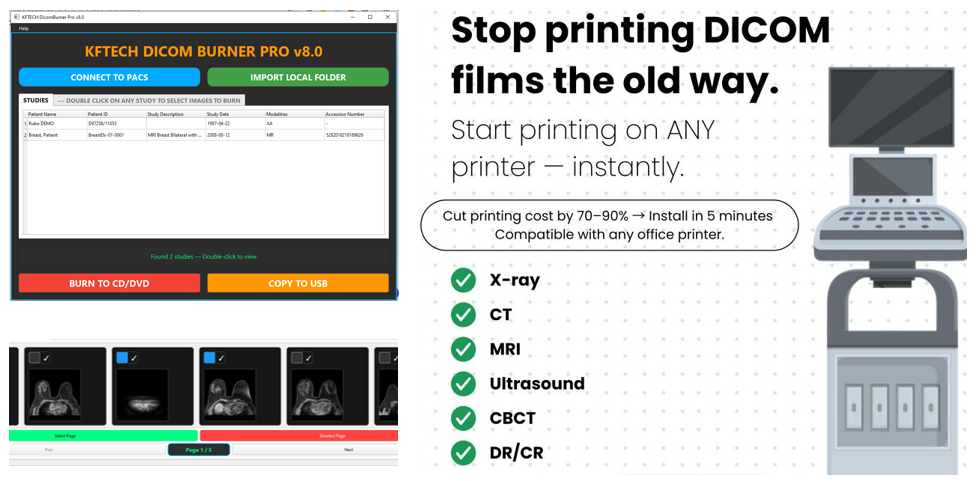

DICOM PrintSCP / CD/DVD/USB Burning Software

We specialize in developing reliable medical imaging solutions tailored to the daily operational needs of radiology departments, diagnostic centers, and healthcare facilities.

We have successfully developed two specialized healthcare software solutions:

◆ PrintSCP Software for seamless printing of medical images from PACS.

◆ CD/DVD/USB Burner Software for burning and distribution of patient imaging studies.

Whether enabling fast and accurate DICOM image printing or ensuring compliant and efficient image sharing via physical media, our solutions are designed to integrate smoothly into existing workflows, enhance efficiency, and support clinical decision-making with precision and reliability.

Solutions

- DICOM PrintSCP.

- DICOM Burner.

- Custom Software.

Services

- Consultancy.

- UI Design.

- Development.

Tech Stacks

- Python.

- PHP Core.

- DotNet Core.